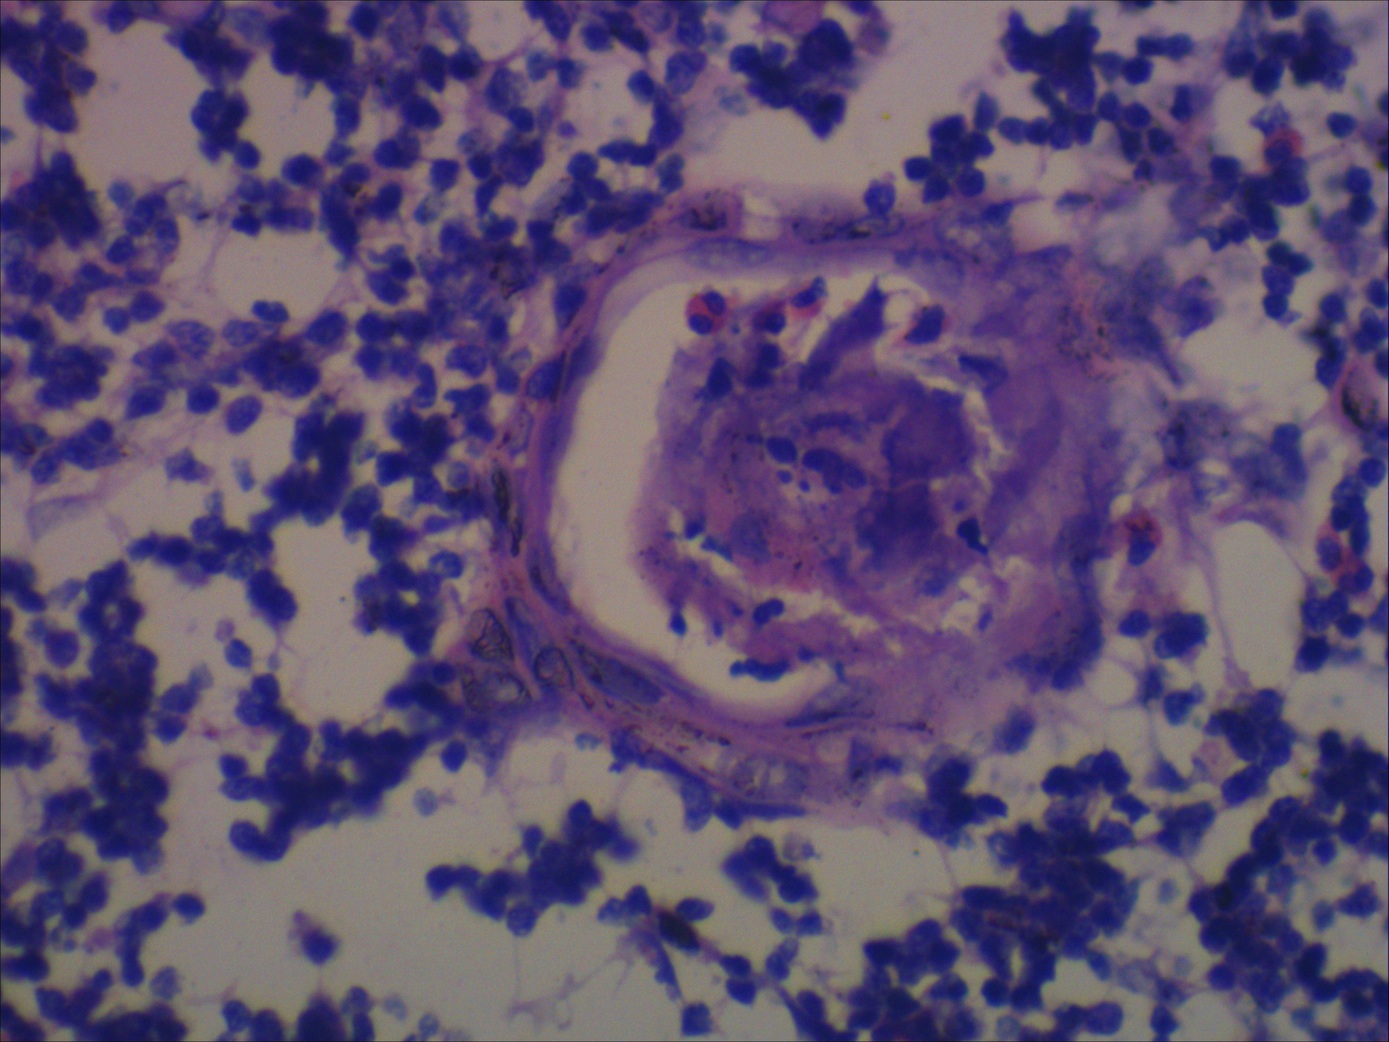

Thymus with ‘thymic lymphoid follicular hyperplasia’ (TFH) in Thymic Hyperplasia Pathology Outlines Uncommon disorder with no / limited symptoms; Defined as the presence of lymphoid follicles in the thymus regardless of the gland size. Benign thymic gland (e.g., thymic follicular hyperplasia, true thymic hyperplasia, sampling bias): 65% of patients have thymic hyperplasia, 25% normal thymus, 10% thymomas; Thymomas are rare tumors arising from thymic epithelial cells with incidence rates of approximately 2.5. Thymic Hyperplasia Pathology Outlines.